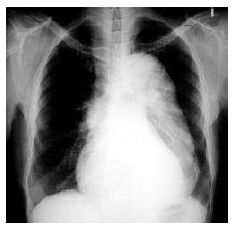

Um homem de 62 anos de idade, com antecedentes de hipertensão e diabetes, procurou o pronto-socorro com relato de dor torácica intensa, lancinante, irradiada para o dorso havia uma hora. No exame, o paciente apresentava fácies de dor, frequência cardíaca de 85 bpm e pressão arterial de 160 mmHg × 80 mmHg. Inicialmente, ele foi submetido a uma radiografia de tórax, cujo resultado está reproduzido a seguir.

Após o exame inicial, a principal hipótese diagnóstica foi confirmada pela angiotomografia.

Nesse caso clínico, a conduta medicamentosa essencial na sala de emergência deve ser composta de